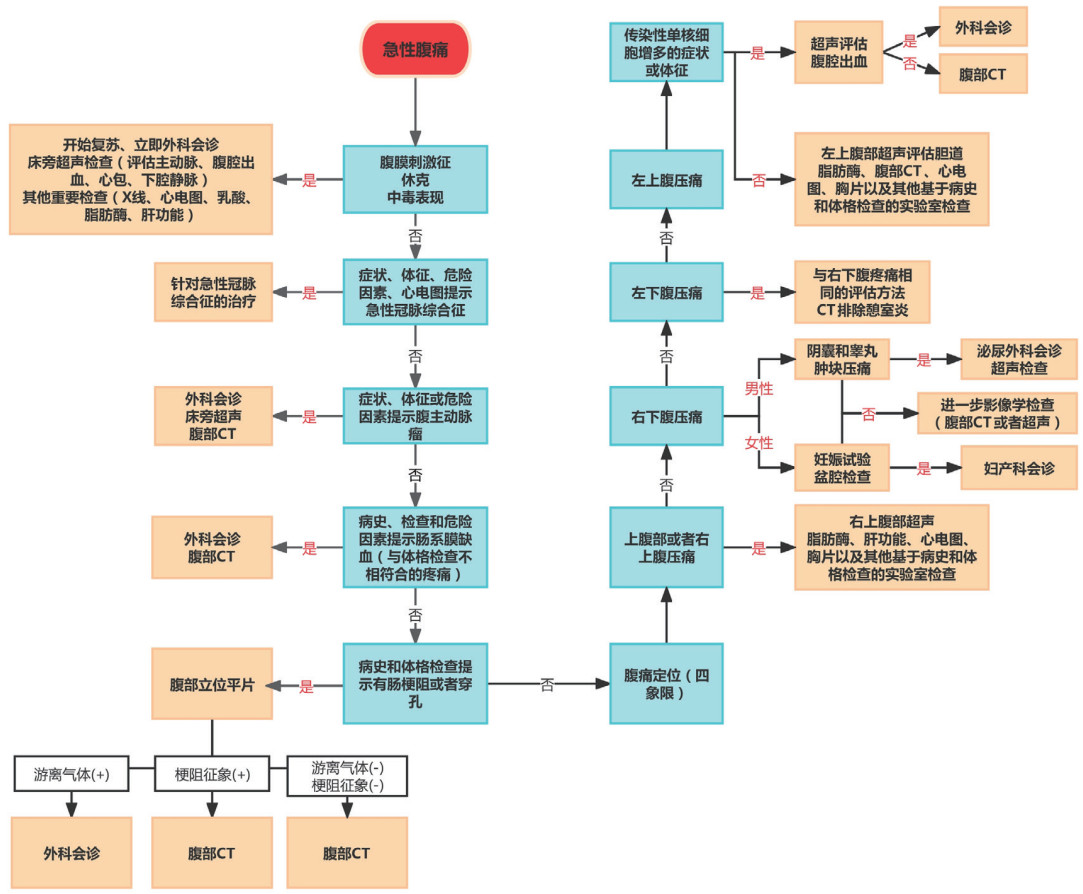

根据既往文献和指南,推荐成人急性腹痛的评估流程[14]如图 2所示,其诊疗原则是:首先寻找可能危及生命的病因,其次针对所有的育龄妇女都应该排除怀孕,积极寻找腹膜炎、休克或者梗阻的体征,腹部影像学检查的意义大于血液检查。

| 图 2 成人急性腹痛评估流程图 |